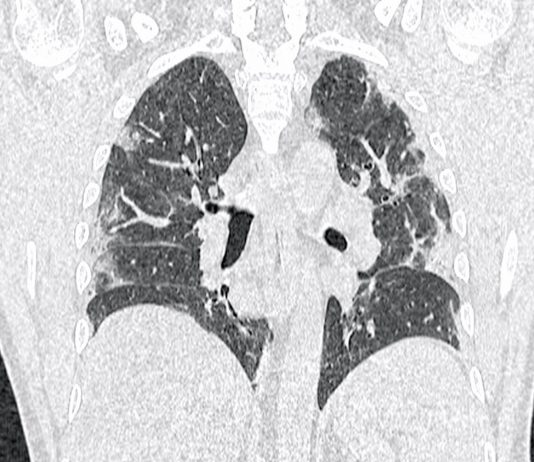

Femmina, 58 anni, asintomatica e apiretica.Esegue come paziente ambulatoriale esterna TC total body per controllo oncologico in neoplasia mammaria, sottoposta nel 2006 a mastectomia con linfoadenectomia, trattata con CT neoadiuvante e RT.